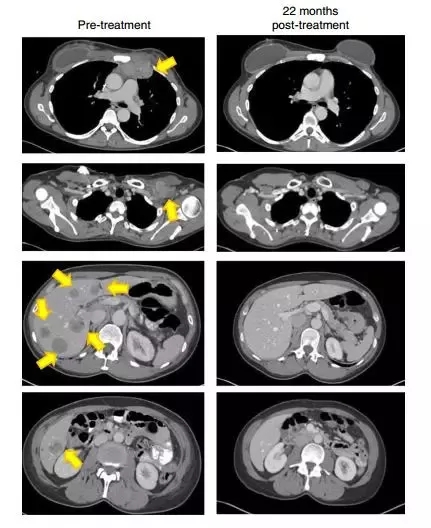

22个月后,影像检查显示(黄色箭头)肿瘤消失得无影无踪(图片来源:《Nature Medicine》)